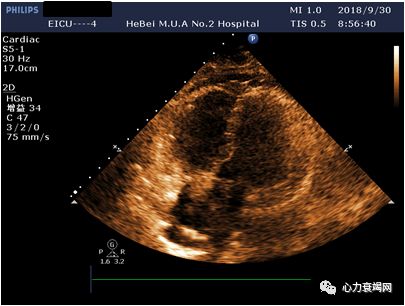

(ECMO第2天,9.30)

心功能较前变化不大

ECMO撤机指征

(4)辅助流量减少到正常心排血量的10%~20%;

(5)超声心动图显示左室射血时间大于200ms,左室射血分数>40%。

心功能较前明显好转,EF50%